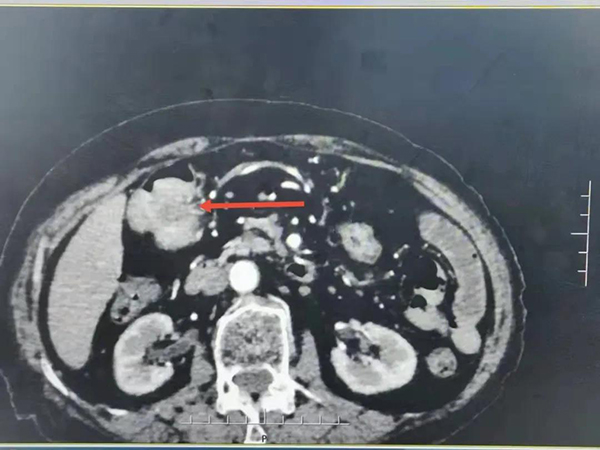

這是一例特殊的病例,患者,女,89歲。既往:便秘病史多年,貧血,心肺功能差。入院后予胃腸減壓、灌腸對癥等治療,但效果不明顯,患者腹部脹痛難忍。腹部增強CT回報:1、結(jié)腸肝曲腸壁不均勻增厚,考慮結(jié)腸肝曲占位可能性大,結(jié)合臨床建議腸鏡鏡檢。

由于老人年事已高,且基礎(chǔ)疾病較多,狀態(tài)差,手術(shù)機會渺茫,且家屬不同意腸道手術(shù)治療。盡快解除患者因腸道梗阻所致的痛苦是當(dāng)務(wù)之急。經(jīng)科室病例討論,消化二科主任孫軍及介入科韓洪武主任為患者量身制定了治療方案,在X線下(DSA)經(jīng)腸鏡引導(dǎo)行支架置入治療。